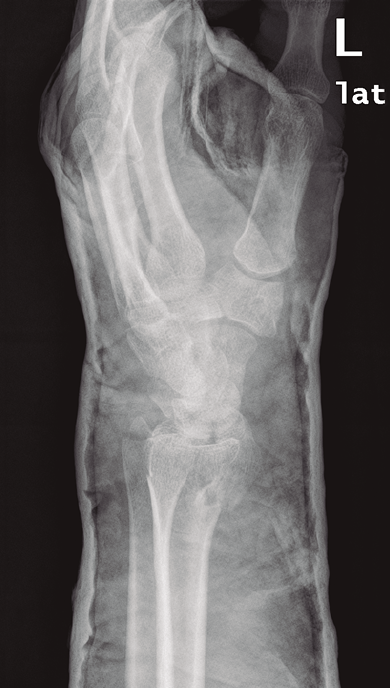

- Artroscopia de muñeca: afectación de la superficie articular, basándonos en los hallazgos observados en el estudio radiológico simple. La presencia de signos sugestivos de lesión ligamentosa en los estudios radiológicos prequirúrgicos constituye un aspecto importante a considerar para asociar una técnica artroscópica al tratamiento quirúrgico convencional. Estos signos radiológicos son: aumento del espacio escafolunar e inclinación dorsal del semilunar en el caso del ligamento interóseo escafosemilunar (Figura 1), la alteración de los arcos de Gilula con solapamiento lunopiramidal para las lesiones del ligamento interóseo lunopiramidal o la presencia de diástasis radiocubital y/o fractura de la apófisis estiloides cubital en lesiones del complejo del fibrocartílago triangular(8,10,20,21). Esto incluye las fracturas que afectan a la apófisis estiloides radial, ya que este patrón de fractura se asocia con frecuencia a lesiones del ligamento interóseo escafolunar(15,17).

Figura 1. Proyección lateral de muñeca con inclinación dorsal del hueso semilunar sugestiva de posible lesión del ligamento interóseo escafosemilunar.